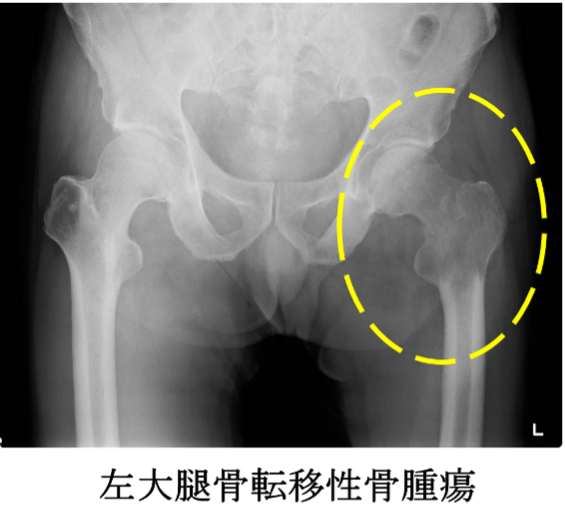

転移性骨腫瘍は、骨の痛みや病的骨折、脊髄麻痺の原因となり、がん患者さんの日常生活に大きな影響を与えます。転移性骨腫瘍の治療は原発巣の治療を行う主治医との連携と、腫瘍に対する幅広い知識が不可欠です。しかし、腫瘍を専門とする整形外科医は少なく、適切な治療を適切な時期に受けられないこともあります。我々は主治医とともに積極的に転移性骨腫瘍の診療に参加し、がん患者さんが失ってしまった日常を取り戻せるよう、また、現在の日常を失わないようにサポートしております。

腫瘍用人工骨頭置換術

当科では、大腿骨近位部の骨腫瘍、特に転移性骨腫瘍に対して腫瘍用人工骨頭置換術を数多く行っております。骨接合術と比較して術後の歩行訓練を早期から行うことができる利点があり、術後の歩行機能も良好です。主に使用しているのはKyocera社のKMLS systemです。幅広いバリエーションが選択できるモジュラータイプのインプラントで、ステムの固定法もセメント固定とセメントレス固定が選べる仕様となっております。